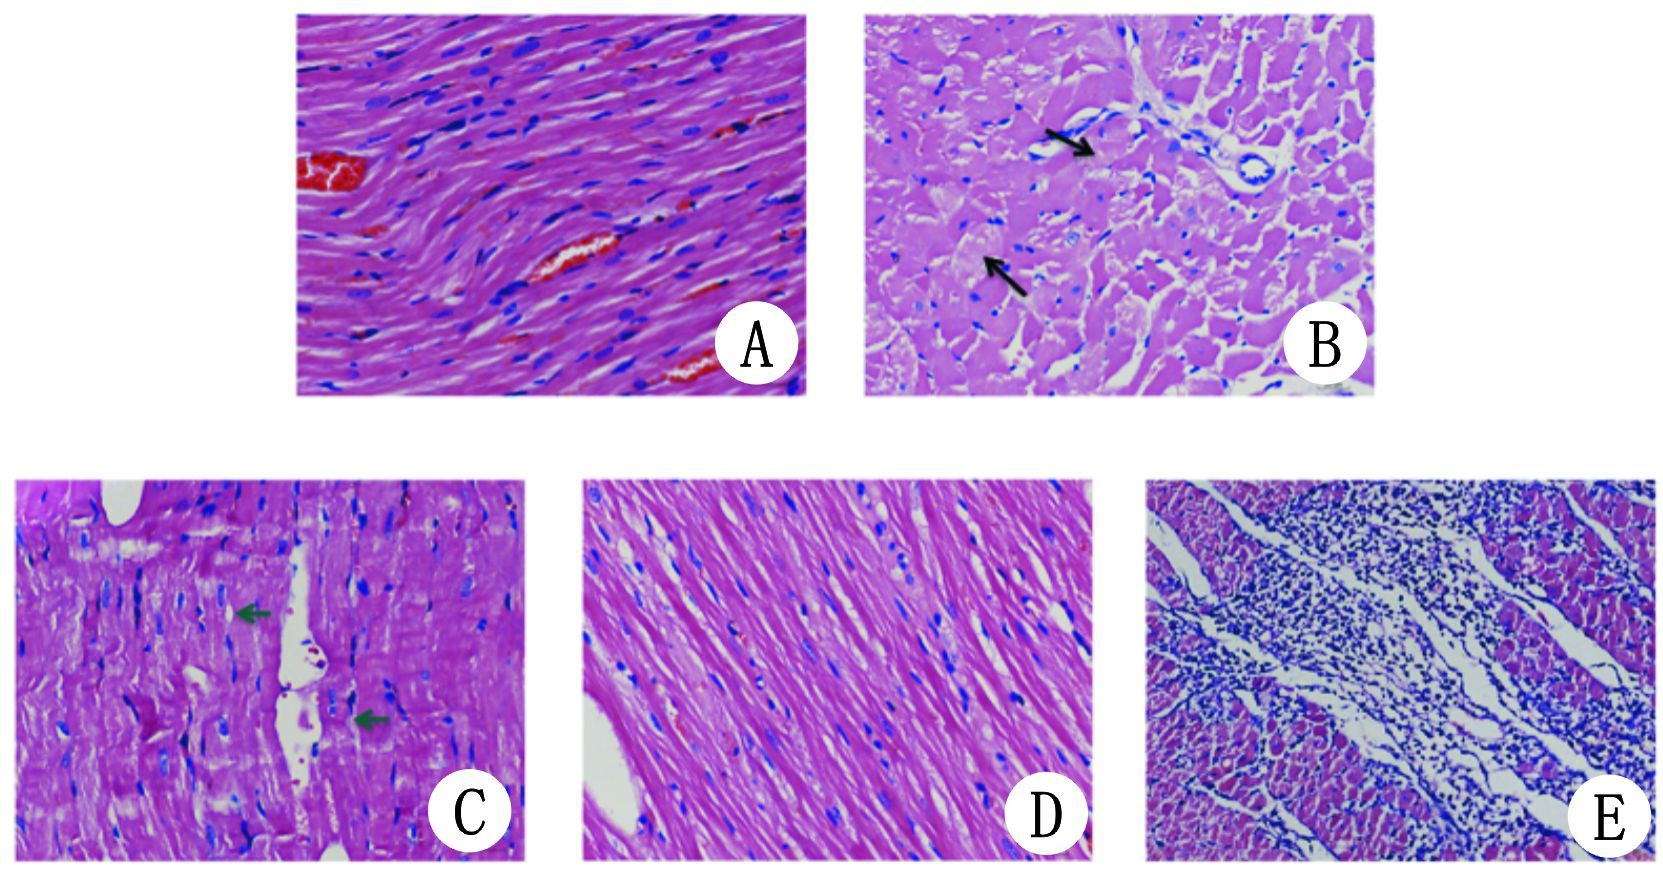

Sham组心肌细胞排列规则,细胞核完整,闺盘清晰。PR 4 h可见心肌细胞肿胀、部分溶解;PR 12 h心肌细胞肿胀更显著,局部肌溶解,可见横向收缩环;PR 24 h无明显肌细胞溶解、肿胀,可见少量炎症细胞浸润和间质细胞增生;PR 72 h心肌细胞排列较紊乱,间质增生显著(图 4)。

| A:Sham组(n=3) ;B:PR 4 h组(n=8) ;C:PR 12 h组(n=7) ;D:PR 24 h组(n=6) ;E:PR 72 h组(n=5) ;黑色箭头所指为肌溶解,绿色箭头所指为横向收缩环 图 4 各组大鼠心肌组织的HE染色 Figure 4 Comparison of HE staining of myocardial tissue among the groups |